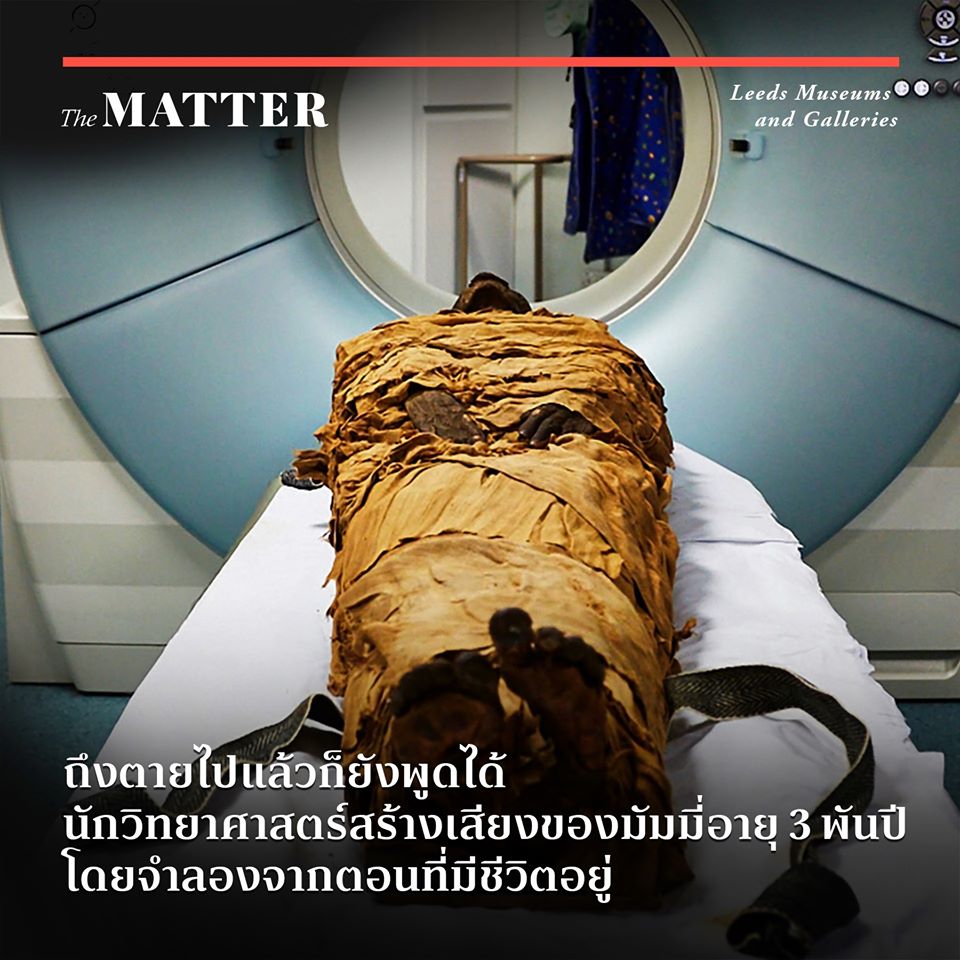

หนังสือ นิตยสาร : *** มัมมี่ ชีวิตหลังการตาย *** เรื่องราวอันลี้ลับ ที่ … ซีที สแกน มัมมี่ เผยความจริง ซ่อนบาดแผลบนพระเศียร ชี้สาเหตุ ฟาโรห์ผู้ …

ซีที สแกน มัมมี่ เผยความจริง ซ่อนบาดแผลบนพระเศียร ชี้สาเหตุ ฟาโรห์ผู้ … ซีทีสแกนมัมมี่ฟาโรห์ เผยเบื้องหลังความตาย ถูกสังหารกลางศึกรบ – ข่าวสด

โลงศพมัมมี่จิ๋ว มัมมี่จิ๋ว แบบจำลองโรงศพจิ๋ว โลงศพมัมมี่ มัมมี่ โลงศพ … นักวิทยาศาสตร์สร้างเสียงของมัมมี่อายุ 3 พันปี – Pantip

นักวิทยาศาสตร์สร้างเสียงของมัมมี่อายุ 3 พันปี – Pantip มัมมี่ของทาโร่ (@karnpitchapp) | Twitter